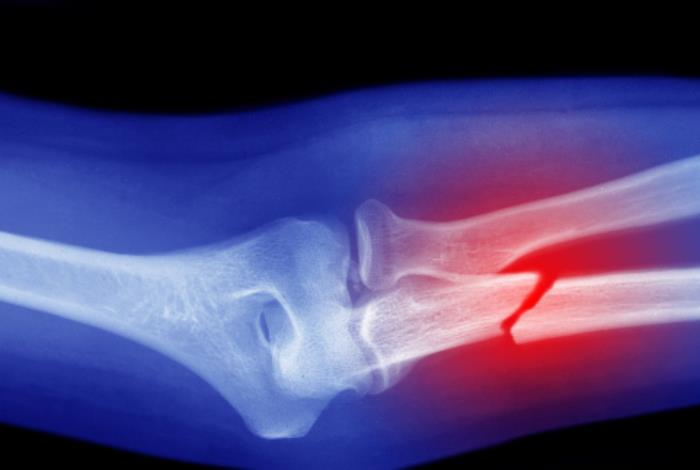

Укреплением костей необходимо заниматься в любом возрасте, ведь это позволит существенно снизить вероятность трещин, переломов и различных заболеваний. Справиться с такой задачей возможно даже без напитков, таблеток и мазей, передает Sports.kz со ссылкой на Hibiny.ru.